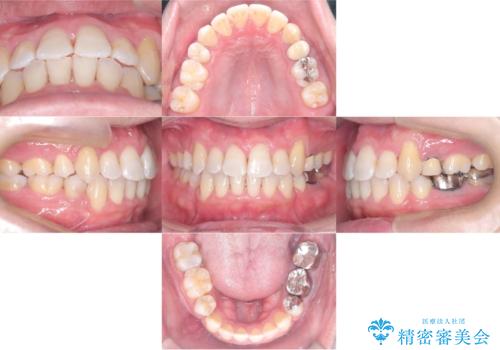

転位歯や埋伏歯などの難易度の高い抜歯矯正治療

【モニター】八重歯と正中を改善 ワイヤー装置の抜歯矯正

担当医 藤巻太一朗